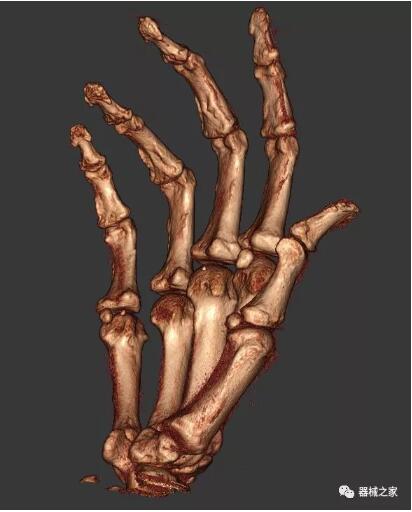

以上介紹的CT均來自國外同一家公司,這些CT均配置了可視化軟件,可以進(jìn)行切片、3D重建以及大型CT附帶的所有典型的操作功能。

以下是這些“特立獨(dú)行”的CT所拍出來的圖像: